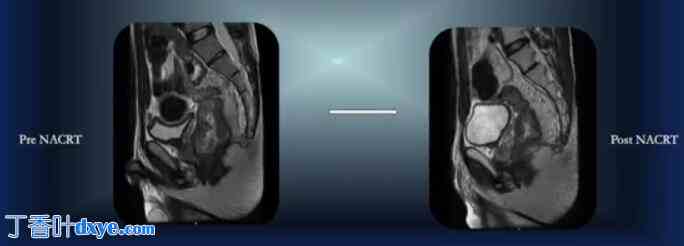

MRI 疗效评估:部分缓解,直肠下段 1/3 处残留 ycT3N1 病灶。无 CRM。

手术时间:NACRT 术后 5 周

计划:腹腔镜全直肠结肠切除术及回肠袋肛管吻合术